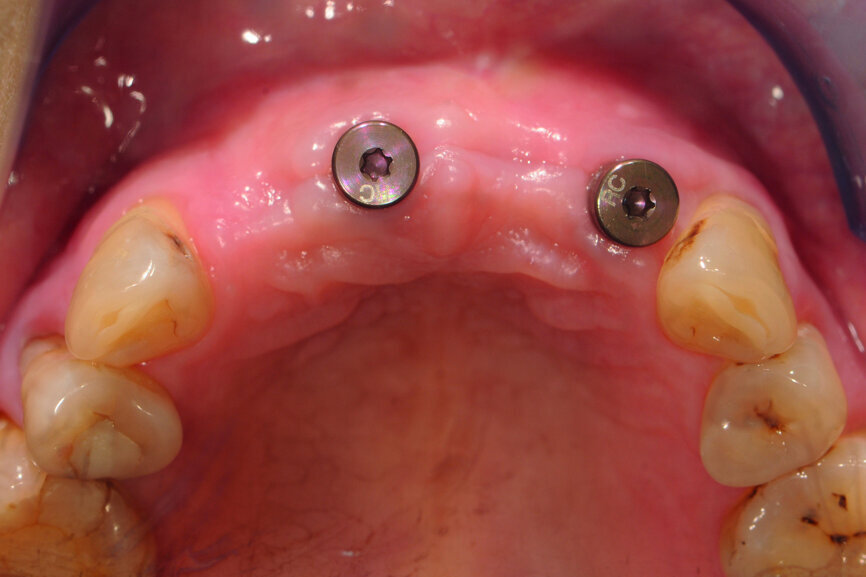

Fig. 5: Frontal view of the anterior teeth immediately post-op.

Fig. 6: Occlusal view of the anterior teeth immediately post-op.

Teeth #12, 21 and 22 were extracted. Tooth #11 underwent early implantation and tooth #22 immediate implantation with GBR (Figs. 5 & 6). After three months of healing, osseointegration had taken place. An implant level impression was taken for fabricating a provisional bridge supported by temporary abutments for teeth #12–22. The technician modified the shape of the artificial gingiva on the model in order to form the proper gingival curve and emergence profile, then finished the provisional bridge, while the dentist modified the gingival shape using an olive-shaped bur intraorally (Figs. 7–18).